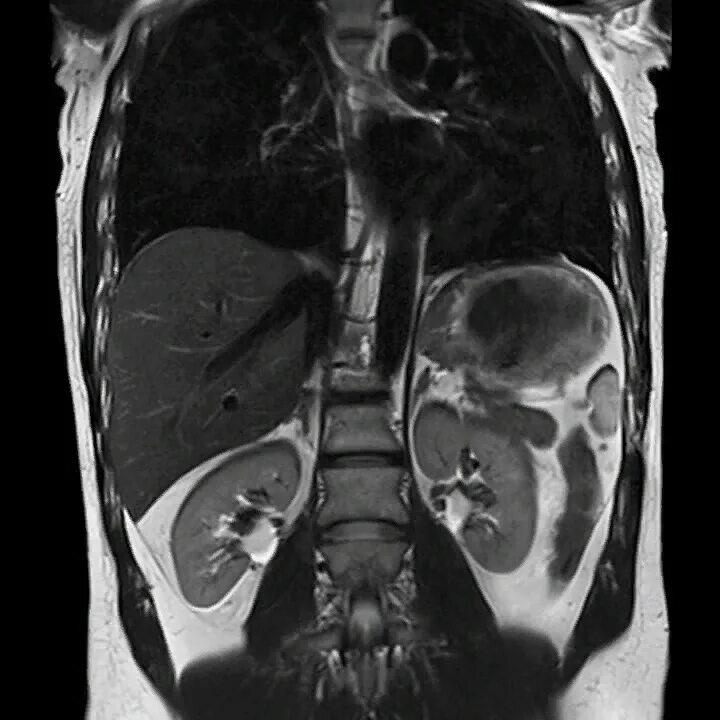

Кт брюшного пространства что показывает